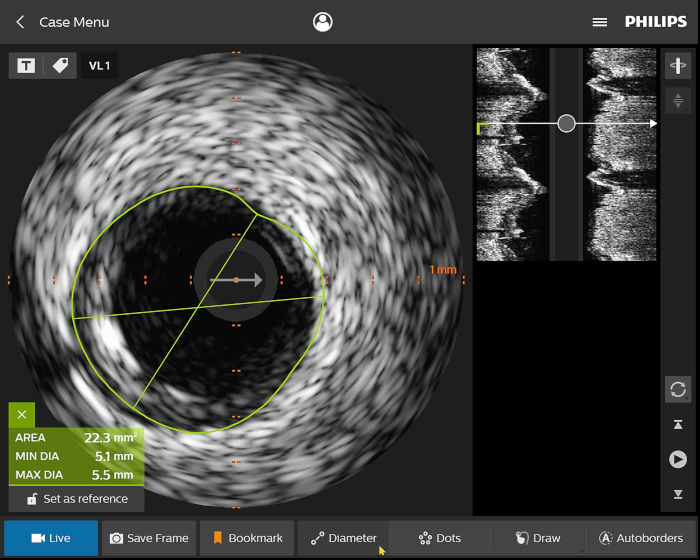

Digital IVUS imaging

imaging

imaging

imaging

Figura 1

Figura 2